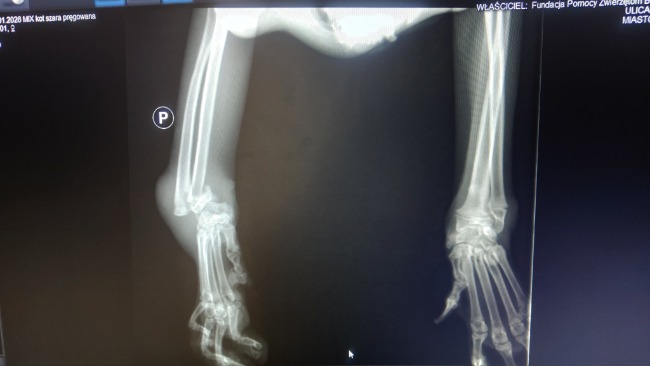

RTG w lecznicy odebrało nam dech.

Ale dramat, który rozgrywa się w ciele tego maleństwa, widać aż za dobrze na jednym obrazie.

Zwichnięcie nadgarstka.

Kości przemieszczone.

Wykręcone wokół własnej osi.